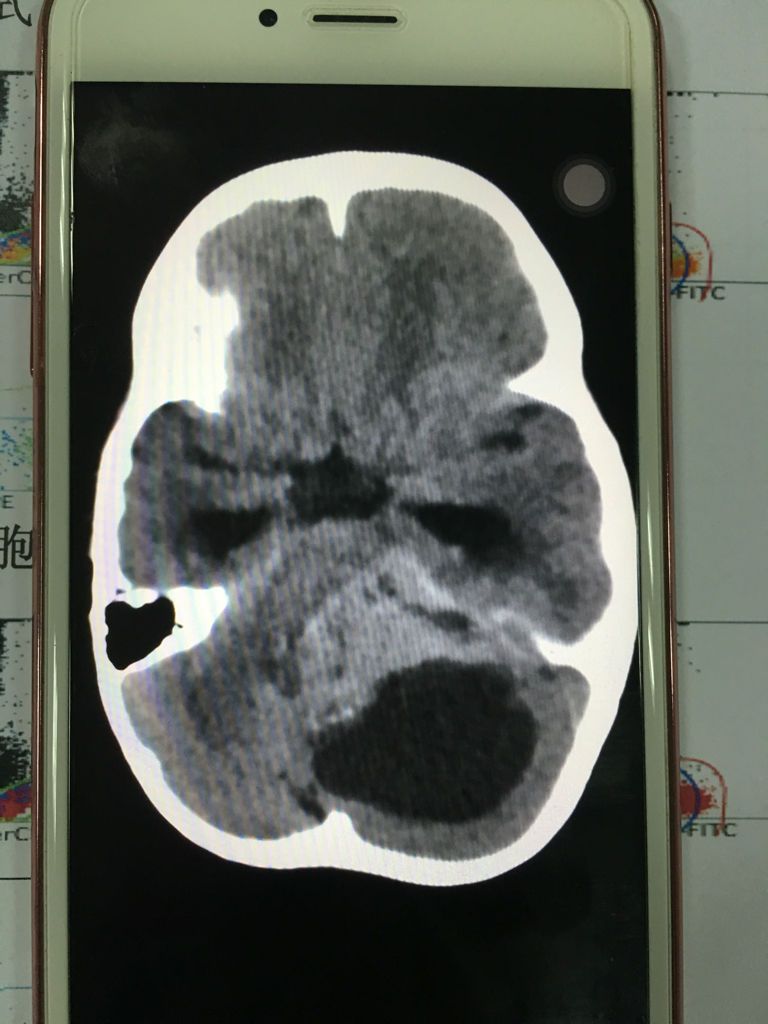

你所说的水母细胞瘤应该是:髓母细胞瘤,它是一种好发于儿童的颅内恶性肿瘤,是中枢神经系统恶性程度最高的神经上皮性肿瘤之一,主要表怪细现为颅内压增高和共济失调等小脑症状常有点堡复视及多种脑神经障碍。医生的孟毯玻意见主要是手术切除与术后放射治疗,部分病例可辅以化疗。